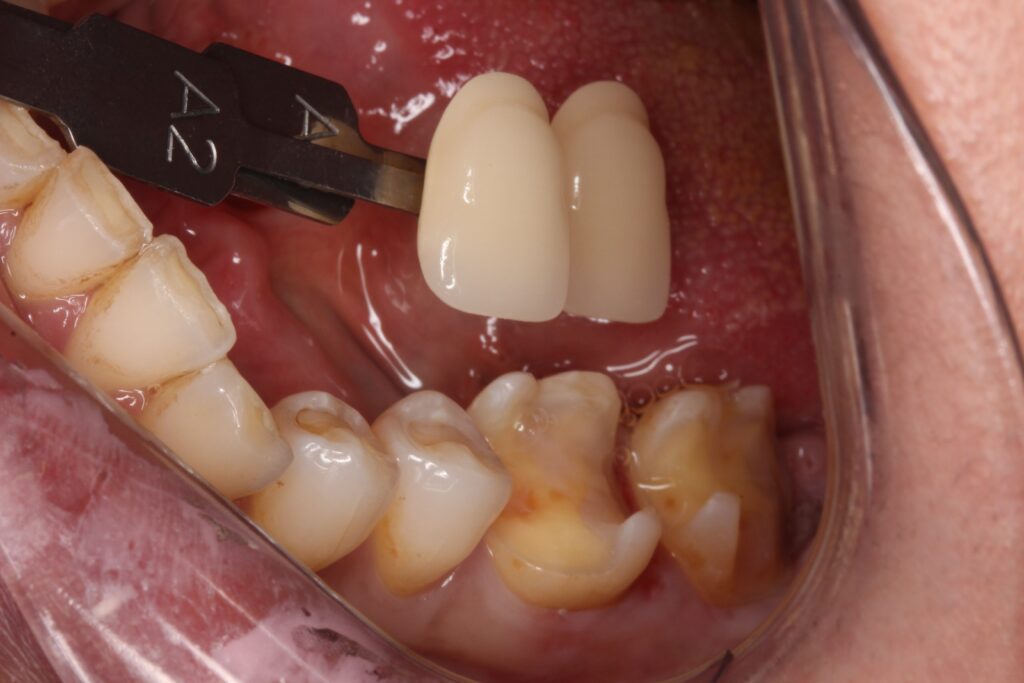

歯の色を記録して、セラミックを製作します。

セラミックがセットされた状態です。

奥歯2本にセラミックが入り、綺麗に歯の形が戻っています(^-^)

一番奥の歯も、親知らずがなくなりすっきりです。